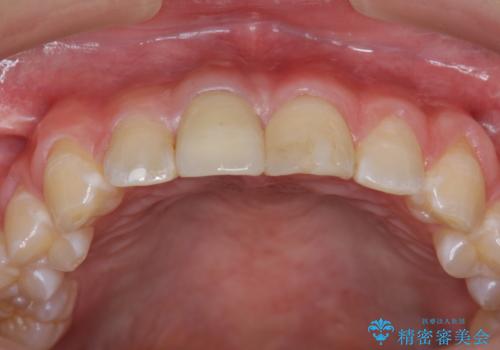

前歯をきれいにしたい ジルコニアクラウンによる審美治療

ジルコニアクラウンによる審美性の改善を計画します。

今回失活歯であったため捻転を取り反対側の前歯に揃えて補綴を行うことができました。